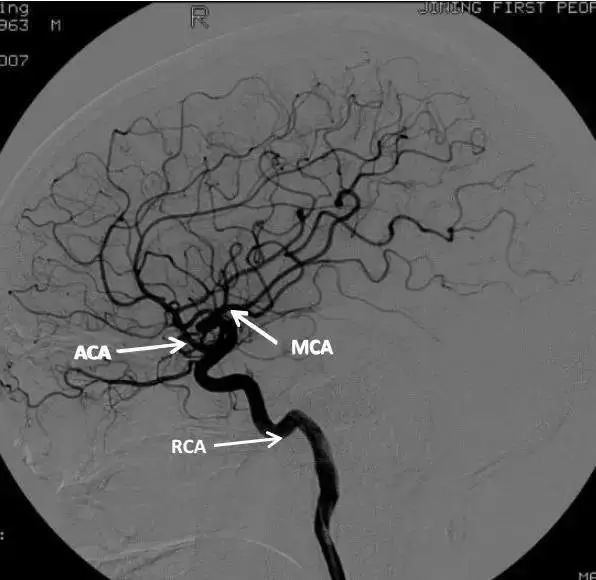

大脑前动脉dsa进阶版

一路向上,颈内动脉分出大脑中动脉和大脑前动脉两大分支,双侧椎动脉汇

大脑中动脉-水平段均可显示.凸面分支不易显示.